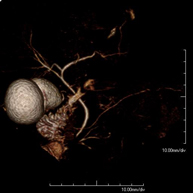

Prova diagnòstica no invasiva que consisteix en l'obtenció d'imatges d'alta definició anatòmica de les artèries cerebrals mitjançant l'ús d'un camp electromagnètic i ones de ràdio (com un emissor i un receptor). No utilitza radiació ionitzant. En la majoria dels casos és necessari l'us de contrast paramagnètic (Gadolino). Permet un estudi angiogràfic no invasiu gràcies a la injecció de Gadolino amb una reconstrucció posterior en 2D i 3D gràcies a estacions de treball especialitzades. Indicacions: malformacions vasculars, aneurismes d'artèries cerebrals, arteriosclerosi. - Angio-RM de troncs supraaòrtics

Prova diagnòstica no invasiva que consisteix en l'obtenció d'imatges d'alta definició anatòmica de les artèries cerebrals mitjançant l'ús d'un camp electromagnètic i ones de ràdio (amb un emissor i un receptor). No utilitza radiació ionitzant. En la majoria dels casos és necessari l'ús de contrast paramagnètic (Gadolini). Permet un estudi angiogràfic no invasiu gràcies a la injecció de Gadolini amb posterior reconstrucció en 2D i 3D, gràcies a estacions de treball especialitzades. Indicacions: malformacions vasculars, aneurismes d'artèries cerebrals i arteriosclerosi. - Angio-RM de Troncs supraaòrtics